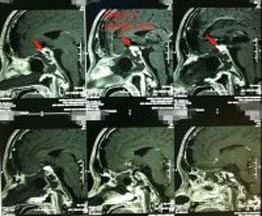

56岁的张先生,3天前出现间歇性头晕,伴有夜间尿多,当地医院就诊,头颅CT检查发现有颅内占位。广东三九脑科医院头颅MRI示:鞍区巨大垂体腺瘤伴瘤卒中,大小约4.3cm×3.1cm×2.8cm,邻近双侧颈内动脉及双侧大脑前动脉受压移位,右侧颈内动脉部分被包绕,视交叉明显受压上抬并向前移位。头颅CTA示大脑前交通囊状动脉瘤,大小约4.6mm×3.4mm。

▲术前MR ▲术前DSA